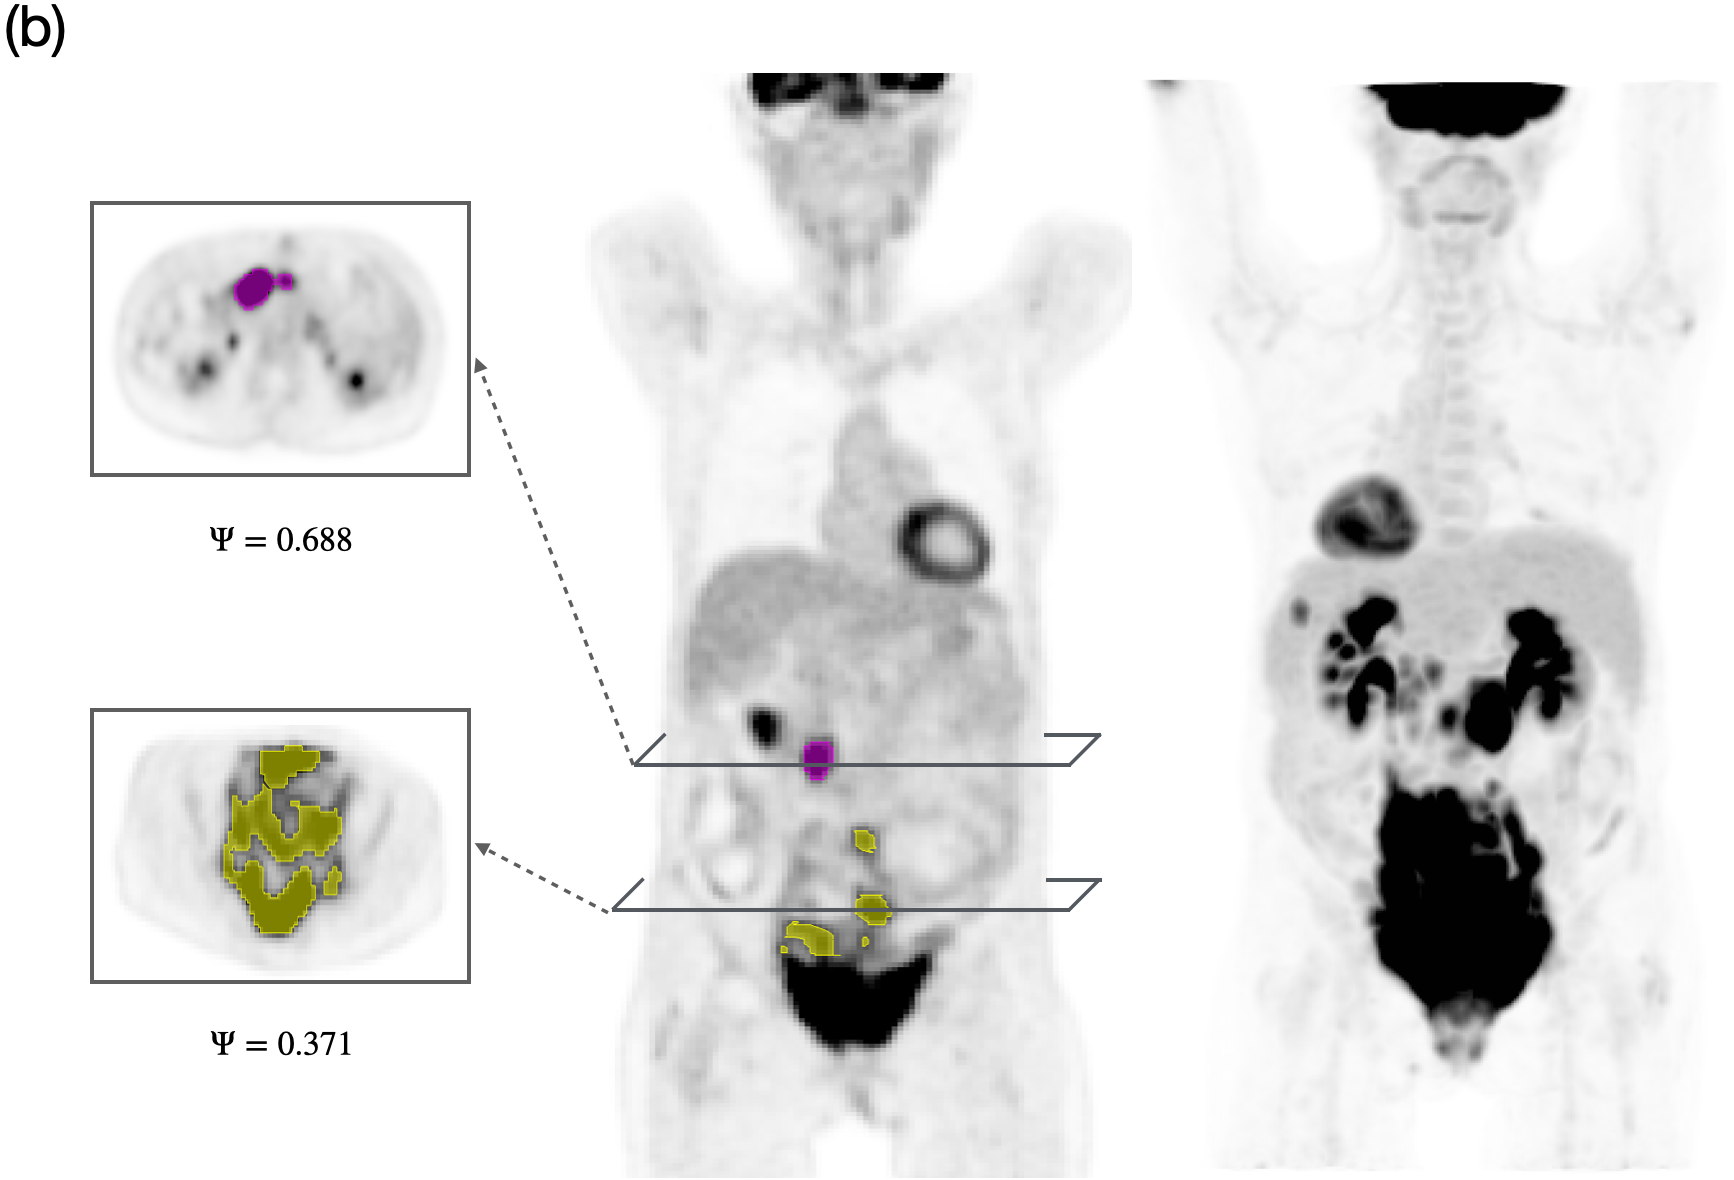

Details of model parameters, as well as their units and values used throughout this study are given in Table 2. We computationally studied the long-term outcome of the treatment by varying the tumor proliferation rate a𝑎aitalic_a and tumor lesion sphericity ΨΨ\Psiroman_Ψ within ranges estimated from literature and our own dataset. Figure 2 shows representative examples of sphericity values observed in 18F-FDG PET images of different lesions from lymphoma patients included in the study. This visualization highlights the morphological heterogeneity among lesions, suggesting that lesion geometry could be a potential factor influencing treatment response and long-term therapy outcome.

Refer to caption

Figure 2: PET/CT images of two different patients showing lesions with varying sphericity values (ΨΨ\Psiroman_Ψ). (a) 3D view of a full-body 18F-FDG PET scan of a lymphoma patient (rightmost image), with the coronal PET scan displaying three lesions of different sphericities, as shown in axial PET slices (leftmost images). (b) 3D view of a full-body PET scan of another lymphoma patient, with the coronal PET scan showing two lesions with different sphericities, along with several axial slices. Higher ΨΨ\Psiroman_Ψ values indicate more spherical lesions, while lower values correspond to irregularly shaped lesions.